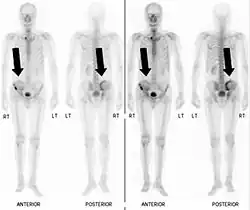

Bone scintigraphy

Also known as a bone scan, bone scintigraphy involves the injection of a small amount of radioactive tracer into the bloodstream. This tracer decays and emits radioactive energy which can be detected by a special camera. The camera produces a black and white image where areas shown as dark black indicate bone damage of some kind. If there is a black spot in the lumbar vertebrae (e.g. L5) this indicates damage and potentially spondylolysis. If this test is positive, a CT scan is usually ordered to confirm spondylolysis.[16]

Commonly known as a CT Scan or CAT scan, this form of imaging uses x-rays to produce multiple cross-sectional images, or "slices", through a part of the body. This allows a physician to evaluate the body in greater detail than an x-ray allows. For this reason the CT scan is much more accurate in detecting spondylolysis than an x-ray. Bone scintigraphy combined with CT scan is considered the reference standard, which means that it is best at detecting spondylolysis.[16][18]